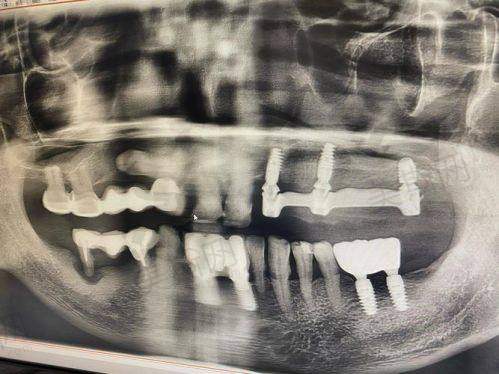

在复杂的口腔手术中,赵延勇和靳小雷医生团队擅长运用显微技术。显微技术在口腔手术中的应用,就如同给医生配备了一双“超级眼睛”,能够更精细地操作,大大降低手术风险。例如在一些种植牙手术中,通过显微镜可以清晰地看到微小的血管和神经,避免手术过程中对其造成损伤,提高手术的成功几率和安心性。

他们在面对各种复杂的口腔情况时,能够凭借不错的医术和丰富的经验,为患者制定个性化的治疗方案。无论是牙齿缺失的修复,还是口腔疾病的治疗,他们都能以专精的态度和高超的技术,为患者解决问题。而且,他们注重与患者的沟通,会耐心地倾听患者的需求和担忧,让患者在治疗过程中感受到温暖和安心。

2. 种植牙技术

- 瑞典诺贝尔系统:该系统骨结合率高,20年存活率超95%。瑞典诺贝尔种植牙采用了精良的材料和表面处理技术,能够促进种植体与牙槽骨的快速结合,为患者提供稳定、持久的牙齿修复成效。

- All - on - 4技术:半口/全口种植采用All - on - 4技术,通过4 - 6颗植体支撑整排牙齿。这种技术减少了植体的使用数量,缩短了治疗时间,降低了患者的痛苦和费用,同时也能达到良好的咀嚼和美观成效。

4. 复杂修复:选择赵延勇、靳小雷等医生团队,利用显微技术降低手术风险。对于一些复杂的口腔修复手术,如多颗牙齿缺失、口腔畸形等,需要专精的医生团队和精良的技术来确保手术的成功。赵延勇、靳小雷等医生团队凭借其丰富的经验和不错的技术,能够为患者提供可靠的治疗方案。